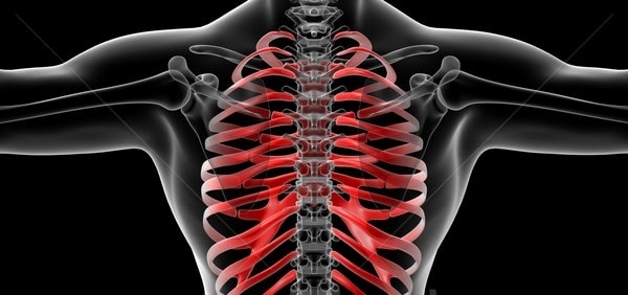

Что происходит с позвоночником?

Перечисленные факторы напрямую влияют на здоровье спины:

- нарушается кровообращение в околопозвоночных тканях, межпозвонковые диски страдают от нехватки питательных веществ (они не имеют собственных кровеносных сосудов и зависят от тканей, их окружающих);

- ослабевает мышечный корсет, поддерживающий позвоночный столб, позвонки получают дополнительную нагрузку, с которой не в состоянии справиться;

- межпозвонковые диски теряют влагу, уменьшаются в объеме и диаметре – позвоночник как бы проседает (многие замечают, что с возрастом становятся на 5, а то и на 10 сантиметров ниже);

- возникает нестабильность одного или нескольких отделов позвоночника;

- организм решает проблему нестабильности, отращивая остеофиты – это краевые костные разрастания, которые со временем намертво цементируют позвоночник, лишая его гибкости.

На заметку. Трансформация позвоночника сама по себе не причиняет боли – болевой синдром появляется, когда происходит ущемление нервных корешков, крупных артерий и лимфатических сосудов остеофитами либо изменившимися анатомическое положение телами позвонков.